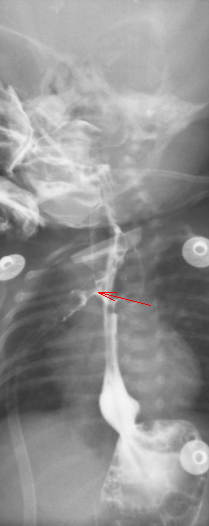

图 3 造影提示吻合口漏持续存在

给予万古霉素抗感染治疗。9.5 腹部彩超:胃内可见少量内容物,余肠管肠腔萎瘪,走形迂曲;腹腔未见明显肠套叠、肠梗阻及阑尾炎征象。9.13 食管造影:食道闭锁术后改变,吻合口漏。贲门位置抬高,建议随诊肺炎。2021-09-28 造影检查: 食管造影:食道闭锁术后改变,吻合口漏,较前稍好转。贲门位置抬高,建议随诊;肺炎;先天性心脏病。磁共振检查 (1T 以上不含 1T): 颅脑 (磁共振功能成像, 平扫):早产儿脑,左侧侧脑室后角室管膜下局灶性脑损伤,小脑幕缘硬膜下少量出血。

入院诊断:入院后完善术前检查,给予箱内吸氧(3L/min),头孢他啶抗感染,维生素 K1 预防维生素 K 缺乏性出血,禁饮食、胃肠减压、补液等对症支持治疗。监测血压、血糖、心电、血氧。确诊食管闭锁。于 2021 年 8 月 19 日行经胸膜外食管吻合术,术后出现吻合口漏,感染指标上升。2021.09.05 根据引流液培养缓症链球菌,药敏结果选用头孢哌酮舒巴坦及万福霉素抗感染治疗,感染指标有所下降,但一直未正常,反复出现喂养不耐受,贫血等症状。先后多次因贫血输红悬液治疗。09.14 停用万古霉素抗感染。2021.09.24,取痰培养,2021.09.25 经验升级抗菌素为美罗培南抗感染。09.26 日行 mNGS 检测。09.27mNGS 结果回报提示为粘质沙雷氏菌,大肠埃希菌,缓症链球菌,产气克雷伯氏菌。同时痰培养结果回报。痰培养结果提示未大肠埃希菌但是几乎全部耐药,仅替加环素敏感。同时提示还有 CMV 感染。考虑多重感染可能性大,继续应用对粘质沙雷氏菌,大肠埃希菌,缓症链球菌,产气克雷伯氏菌等病原均有作用的美罗培南抗感染,同时停用对耳肾毒性较大的万古霉素抗感染。患儿精神状况好转,感染指标逐渐下降至正常,喂养耐受,肠内营养增加,贫血改善。2021.10.09 血常规及 c 反应蛋白正常,感染控制。2021.10.19 复查造影提示吻合口漏愈合(图 4)。10 月 22 日因食管狭窄再次行食管狭窄扩张治疗,术后恢复顺利,10.28 达到临床治愈出院。